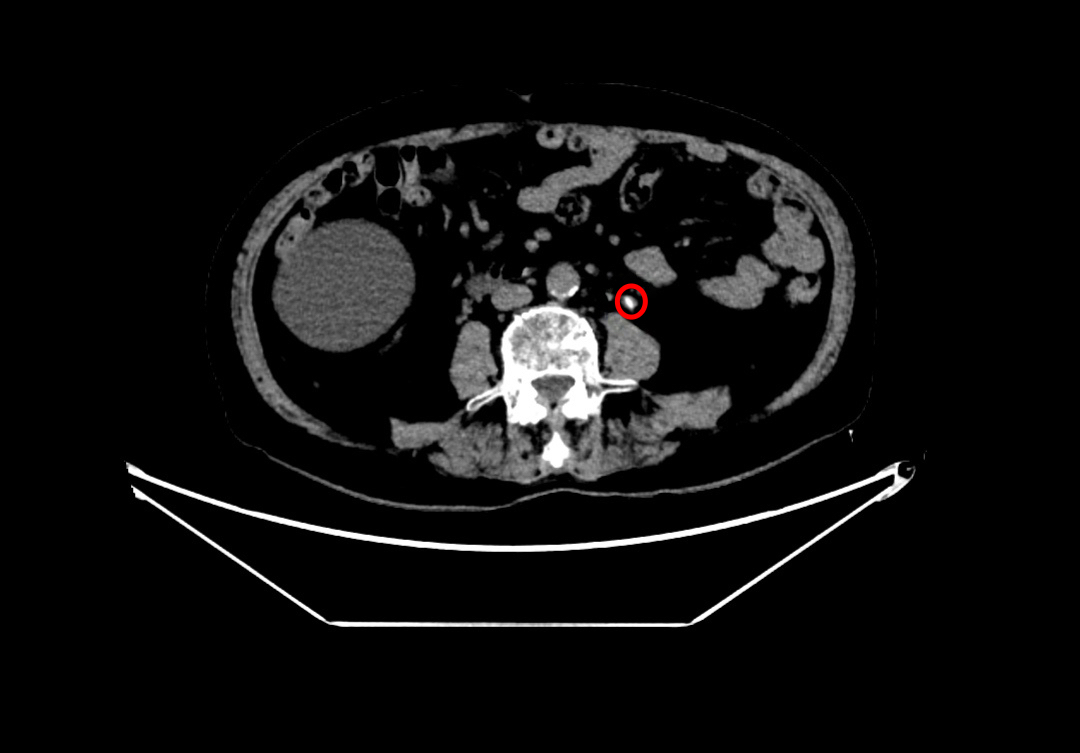

术前左侧输尿管结石

术前左肾结石

在魏武然主任医师和麻醉手术中心李晓强副主任医师的带领下,泌尿外科和麻醉科医疗团队对何爷爷进行了全面的术前评估,并针对可能出现的各类风险制定了周密的手术方案及应急预案。9月9日,手术如期进行。术中发现患者左肾中下盏存在多发结石,最大约2cm×1.5cm,质地坚硬,同时左输尿管上段见数枚不规则小结石,整体结石负荷大、分布复杂,进一步增加了手术难度。